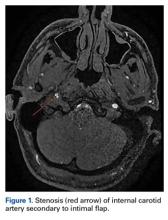

Magnetic resonance imaging of the head and neck was normal, but magnetic resonance angiography (MRA) of the neck showed a 1-cm-long region of the ICA, before piercing the petrous bone, with evidence of dissection.

There was an associated intimal flap and about 50% luminal narrowing (Figure 1).Given the normal neurologic examination, and no evidence of brain infarction or other neurovascular complications, the acute ICA dissection was managed with antiplatelet therapy using aspirin (325 mg/d). In addition, the patient was advised to refrain from strenuous physical activity and to present to the hospital immediately if symptoms worsened or any neurologic impairment developed. Follow-up and repeat MRA were planned to monitor healing progression.